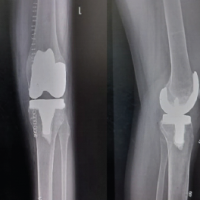

The radial head osteotomy with resurfacing was done (Fig. 5b) as planned pre-emptively on our 3D model, and fixation and alignment were done and held in place using AO 5-holed radial head ring plate (Fig. 6a). Fluoroscopy was used to confirm appropriate articular reduction and position of implants in situ. Intraoperatively, full range of motion was executed passively on the table. The elbow joint appeared to be stable throughout its range of motion. The wound was closed in layers, and sterile dressing was done. Post-operative X-rays were taken (Fig. 6b and c). The patient was placed in an arm pouch. Dressing was done once every 3 days.

The patient was reviewed 1 year 6 months after surgery and presented with full, painless range of motion of the left elbow compared to the opposite side (Fig. 7). Radiographs taken showing union of radial head at the time of follow up (Fig. 8). The patient also underwent implant removal before skeletal maturity to allow the natural course of remodelling and preventing limb length discrepancy (Fig. 9).